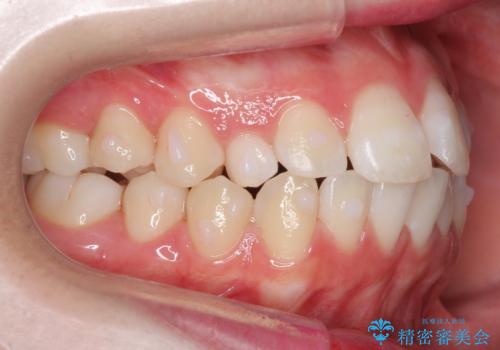

前歯のがたつき 乳歯を抜かずに矯正

- 前歯のがたつきを主訴に来院。

右上に乳歯が残っていましたが、後継永久歯がないため、抜かずに矯正しました。

乳歯の部分が反対咬合でしたが、歯列矯正で被蓋が改善するように移動させました。

右上の乳歯は移動させましたが、幸い矯正後にぐらつくこともなく、そのまま抜けるまで使うことにしました。